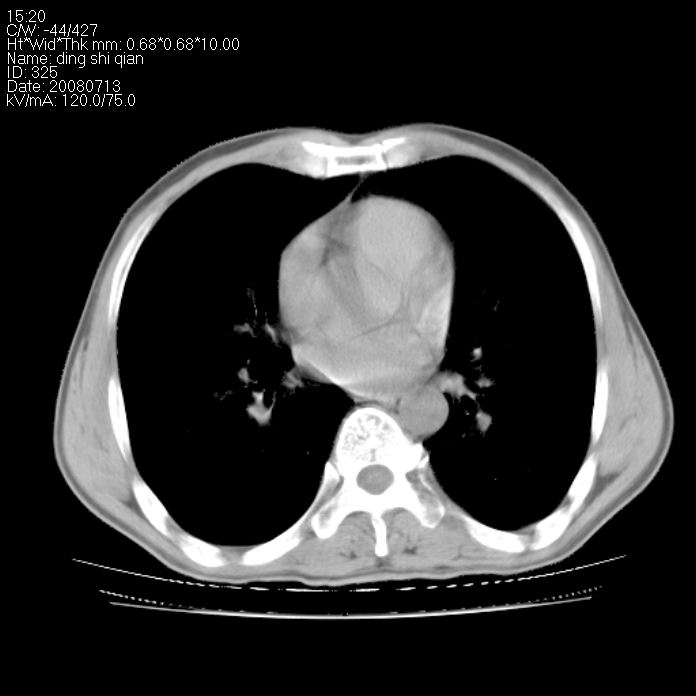

标题: CT14654:男 50岁 近来胸痛 [打印本页]

标题: CT14654:男 50岁 近来胸痛

右侧上肺块状软组织影,浅分叶,边缘毛刺证,与胸膜粘连,考虑:周围性肺癌

右侧上肺块状软组织影,浅分叶,边缘毛刺证,与胸膜粘连,考虑:周围性肺癌!支持!